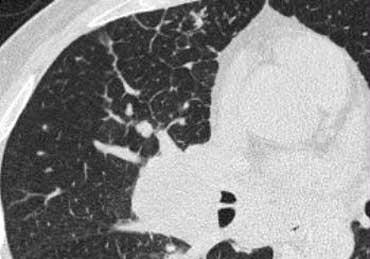

Sarcoidosis: hình ảnh điển hình với các nốt dọc theo bó mạch phế quản và các khe liên thùy. Lưu ý hạch vôi hóa một phần ở rốn phổi trái.

Bên trái là một hình ảnh điển hình khác của sarcoidosis với hạch to trung thất và các nốt nhỏ phân bố theo đường bạch huyết dọc theo bó mạch phế quản và dọc theo các khe liên thùy (mũi tên vàng).

Luôn tìm kiếm các nốt nhỏ dọc theo các khe liên thùy, vì đây là dấu hiệu rất đặc hiệu và điển hình của sarcoidosis.